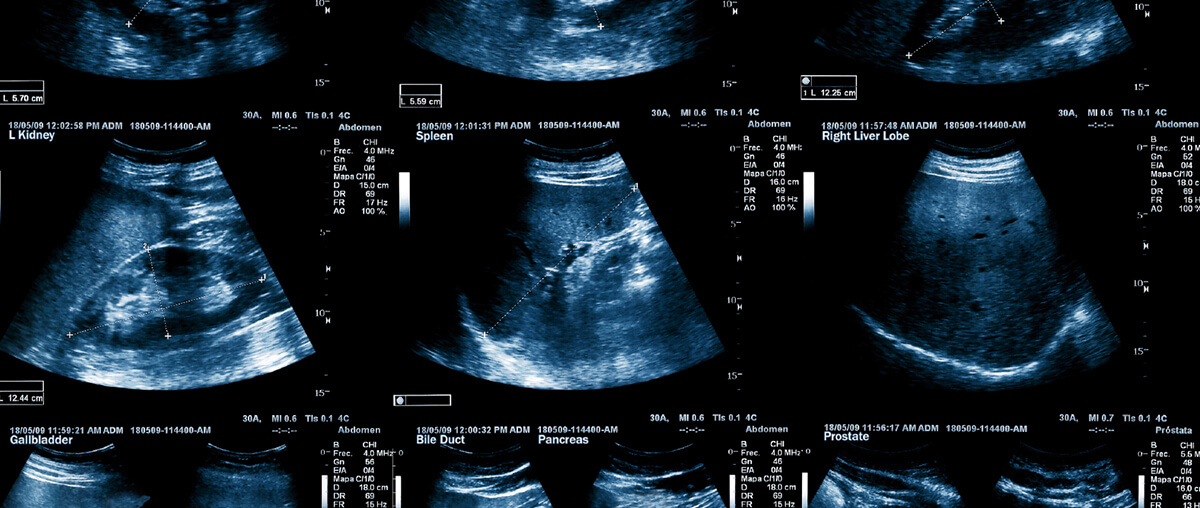

Our ultrasound solution provides everything to perform ultrasound exams in your office.